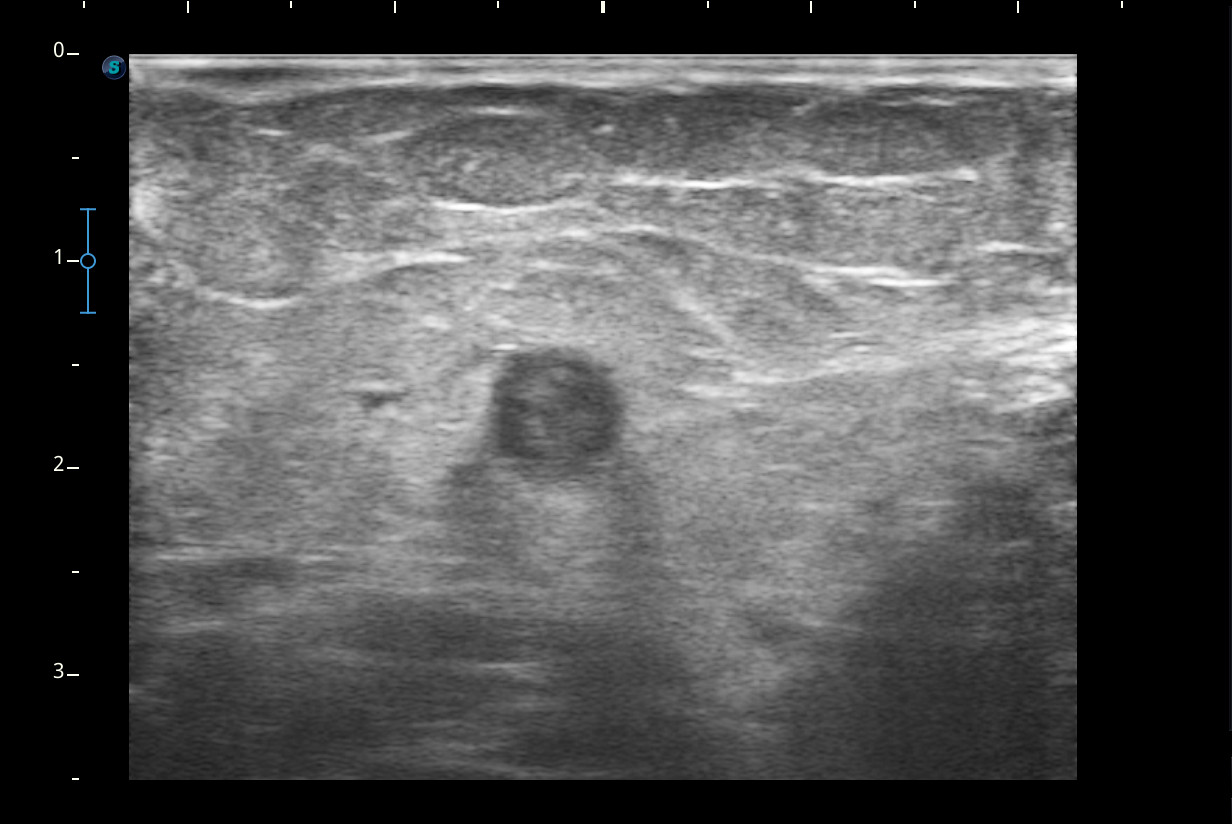

Se visualiza congestión del tejido subcutáneo del brazo y ocupación de la luz de la vena basílica del brazo por un trombo.

Diagnóstico: trombosis venosa de la vena basílica del brazo derecho. Concordancia con el hospital en el segundo tiempo que acude la paciente.